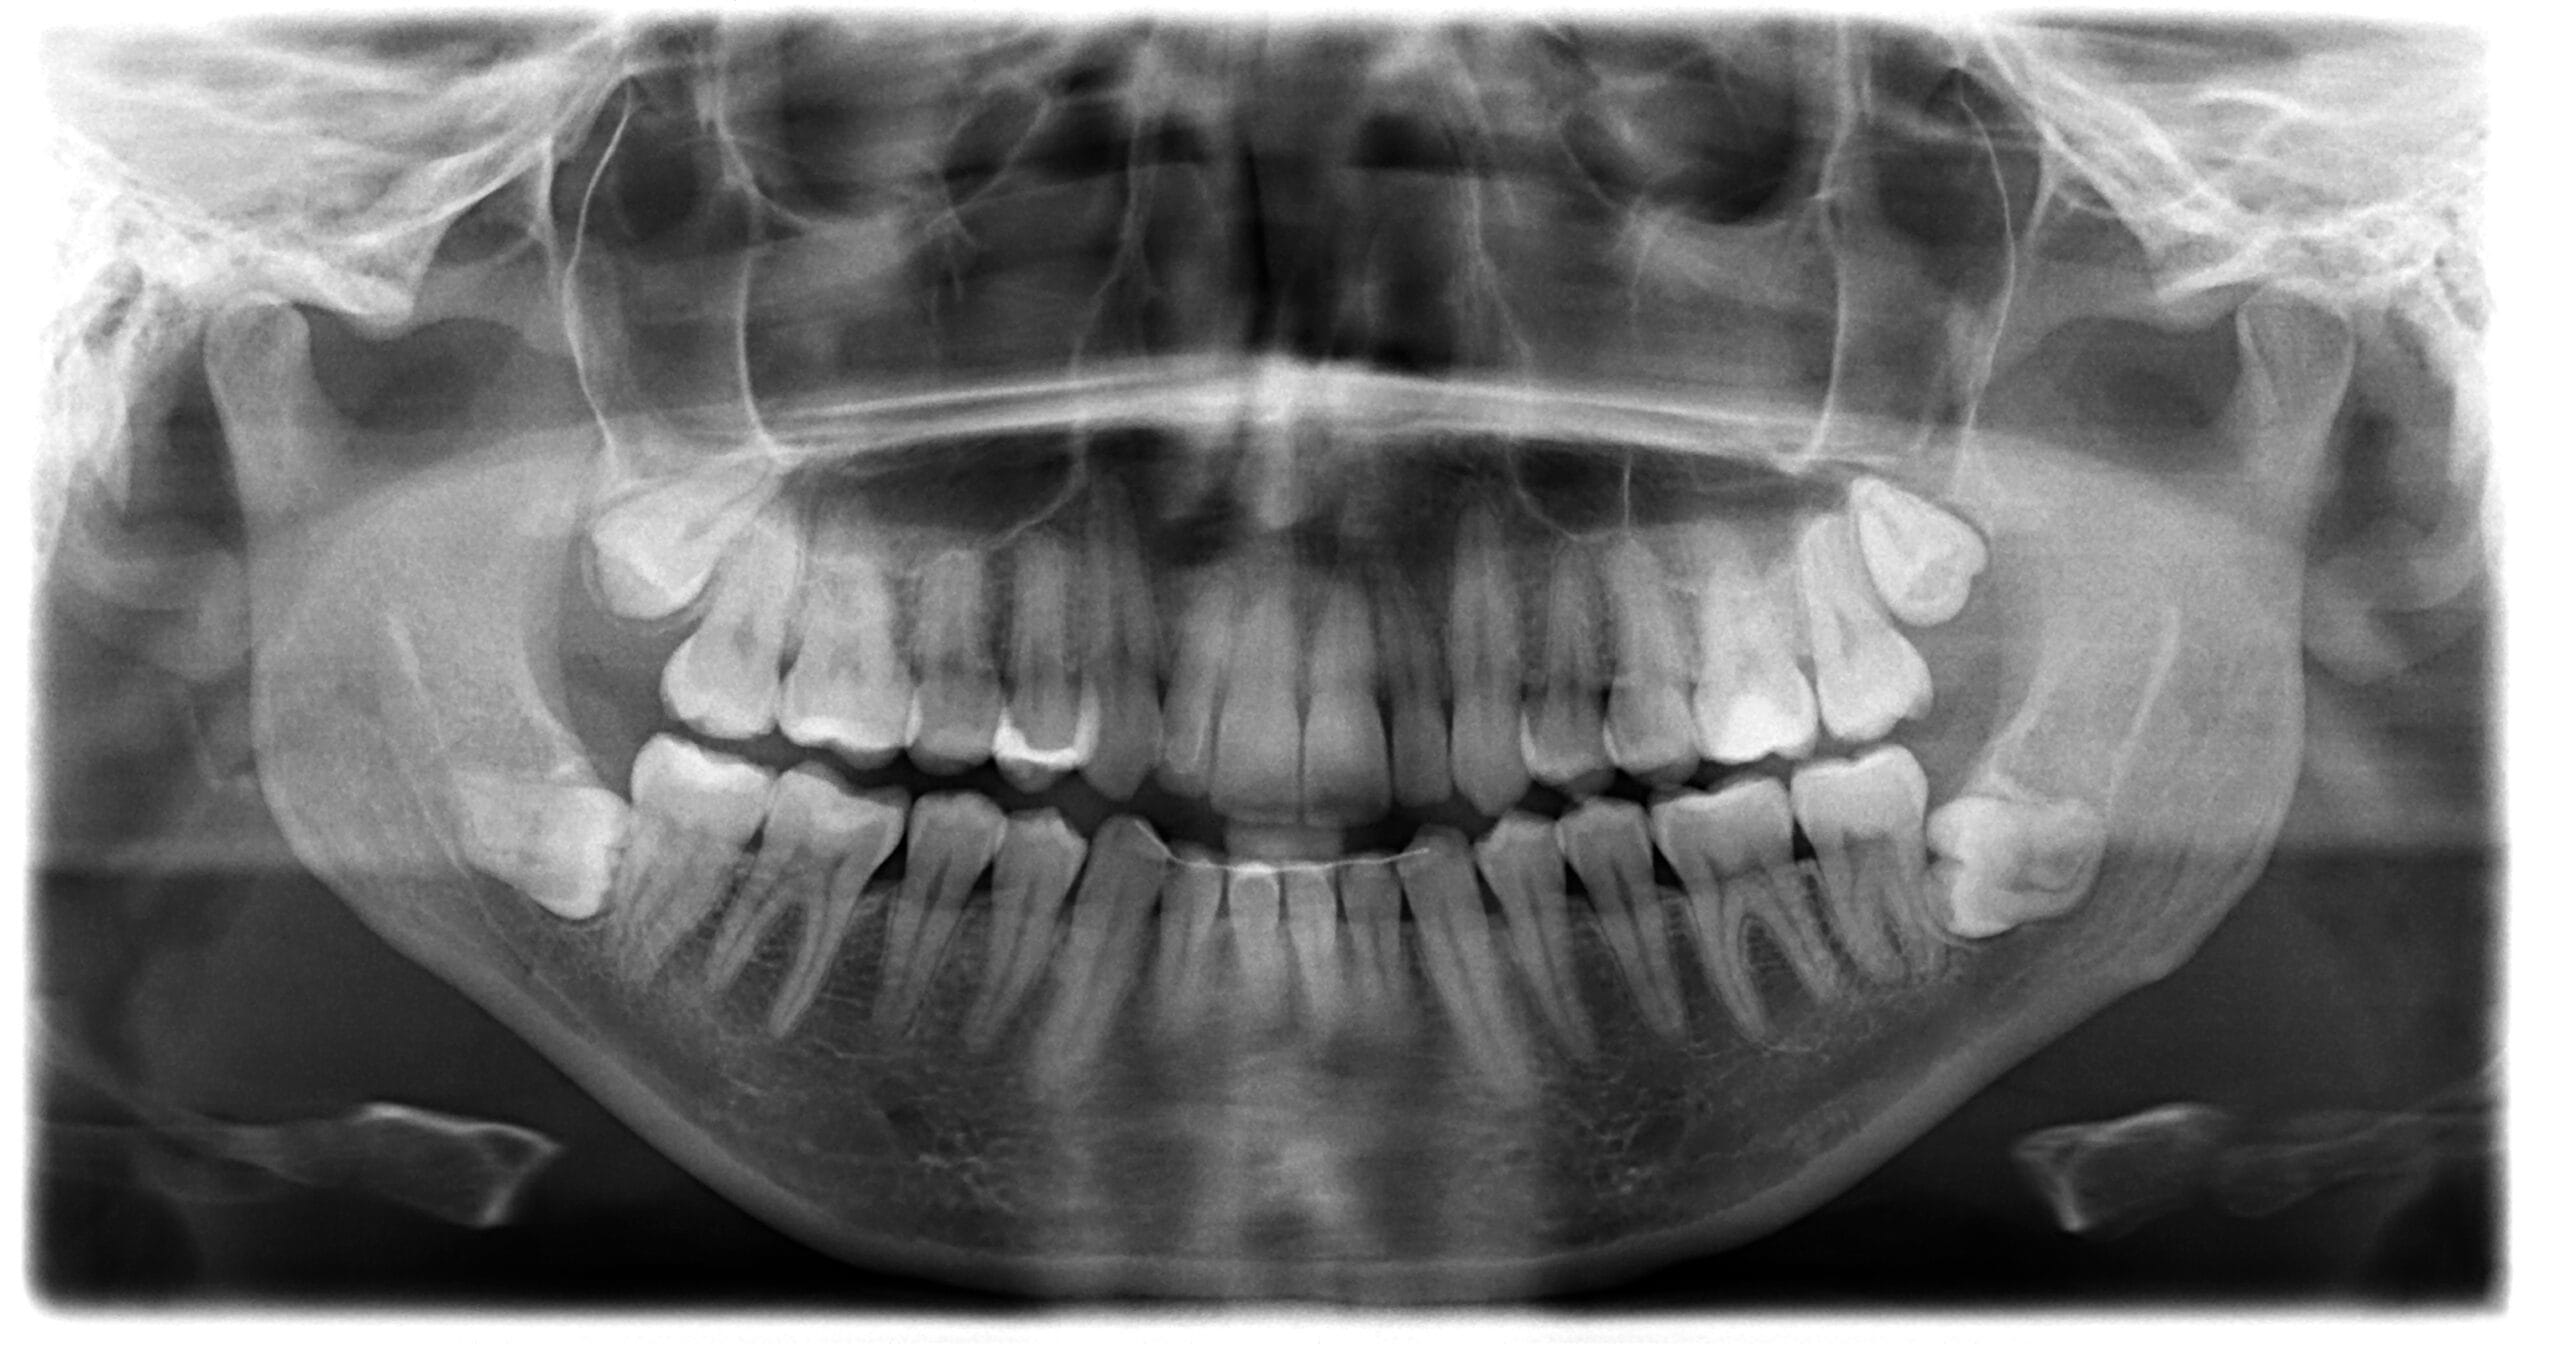

Dental X-rays (radiographs) are images that show the structures inside your mouth that aren’t visible during a regular dental exam. These images capture your teeth, the roots beneath your gums, and your jawbone, revealing potential issues like decay between teeth, bone loss, impacted teeth, abscesses, or cysts. Different types of X-rays serve various diagnostic purposes, ranging from detecting cavities to planning orthodontic treatment or dental implants.

Our office utilizes Cone Beam Computed Tomography (CBCT) technology, an advanced imaging system that creates detailed 3D images of your teeth, soft tissues, nerve pathways, and bone in a single scan. This technology provides unparalleled diagnostic capabilities for complex cases, helping us plan dental implant placements with incredibly detailed images, visualize root canal anatomy, and evaluate jaw disorders. CBCT imaging aids significantly in TMJ/TMD therapies and orthodontic treatment planning by giving us a complete view of your oral structures and their relationships to provide more predictable treatment outcomes.

Dr. MacPhail, DDS personally reviews your dental history and discusses any specific concerns before recommending X-rays. She explains which types of dental images will provide the most accurate diagnosis for your unique oral health situation. Our team considers your overall health background, including previous dental work and medical conditions that might influence our imaging approach.